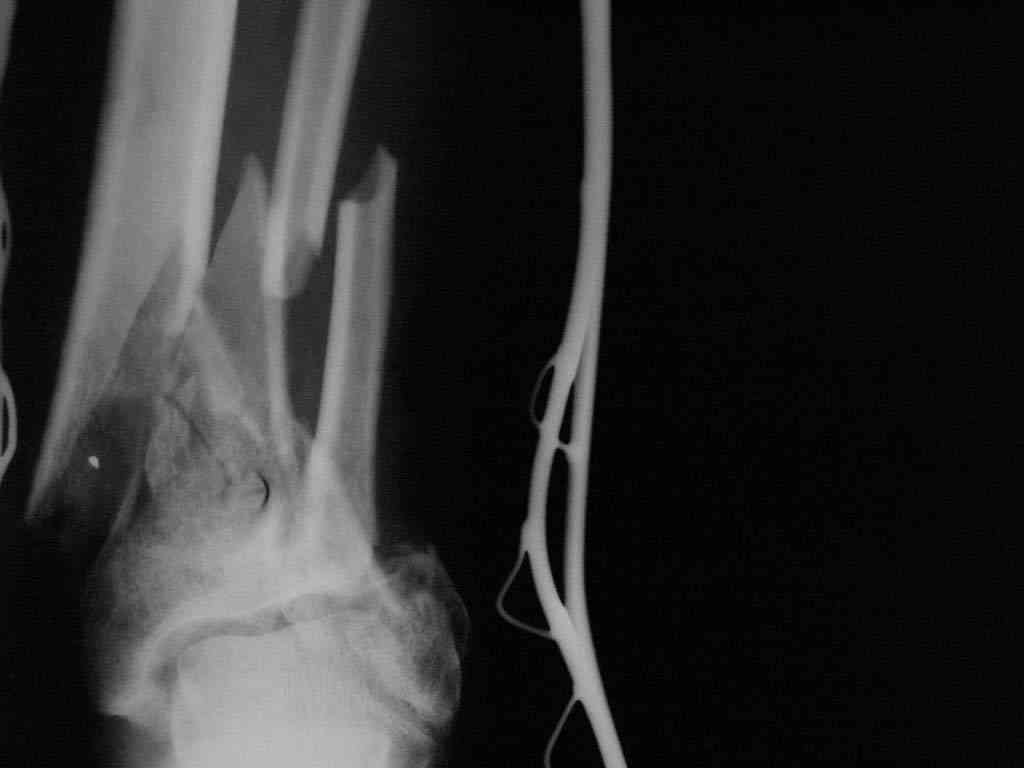

Сочетанная травма. Ушиб головного мозга лёгкой степени тяжести. Компрессионные переломы тел 12 грудного и 5 поясничного позвонков без неврологических осложнений. Закрытый внутрисуставной многооскольчатый перелом дистальных метаэпифизов обеих костей правой голени со смещением. Открытый внутрисуставной многооскольчатый перелом дистальных метаэпифизов обеих костей левой голени со смещением (см. Р-граммы). Хронический алкоголизм.

В последующем перевязки раны с "Левомеколь", через 3 недели с момента травмы в ране определялись грануляции, нежизнеспособный конец дистального отломка. 10.11.08 ВХО раны, резекция дистального отломка на 3 см, перемонтаж аппарата наружной фиксации (см. Р-граммы). Отломки сближены на 2 см (остеотомию малоберцовой не делали). В настоящее время (5 сутки после операции) незначительное количество серозного отделяемого из раны, имеется дефект кости 4 см (см. Р-граммы).

Представляем рентгенограммы левой голени при поступлении, после повторного оперативного лечения и фото st.localis на 14.11.08.